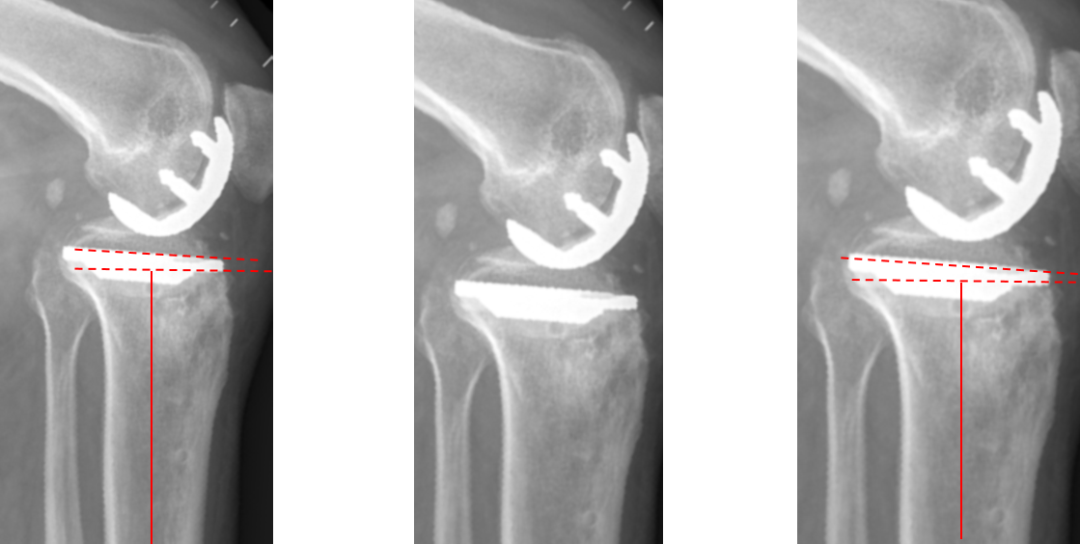

二、外侧SIGMA:registered: HP KNEE假体位置

标准胫骨假体位置

AP位胫骨与股骨假体位置:胫股角10°,轻度膝外翻;水平截骨轻度外翻,外侧缘与胫骨平台外侧缘齐平; 股骨假体中轴线与胫骨假体垂直,股骨假体中心与胫骨假体中心一致。

侧位片胫骨与股骨假体位置:胫骨假体后倾7°,前后缘齐平;股骨假体后倾15°;股骨远端截骨面与股骨髓腔中心线垂直,完整包容股骨后髁。

外侧间隙过分填塞(膝内翻)

AP位胫骨与股骨假体位置:胫股角-2°,膝内翻;屈曲间隙过份填塞,关节线上移,股骨假体外翻。

股骨假体过屈(皮质损伤)

侧位股骨假体位置:股骨远端后倾15°截骨,导致后髁115°截骨,后侧皮质损伤。

股骨假体过伸

侧位股骨假体位置:股骨远端前倾10°截骨,导致股骨股骨后髁截骨与股骨髓腔中心轴平行,股骨假体过伸。

股骨后髁过截

外侧股骨髁坏死伴发育不良。

股骨假体过屈

外侧单髁术后股骨后髁过截,股骨假体过屈(45°)。